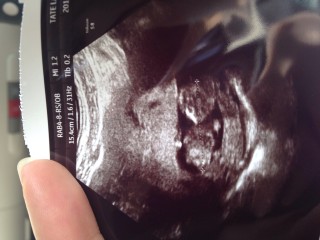

仕事が大変で体と心に負担かけてしまっていたので、お腹の赤ちゃんの様子が心配でした。ですが写真の通り。こちらを見て笑っているようで、、感激です!

9wから倍以上の大きさ、46.6mmになってて、 エコー画面を見た瞬間思わず「でかっ」と言ってしまいました。 角度によって頭蓋骨の目鼻口も見えました。 ちっちゃいドクロちゃんですが、気持ち悪いとかではなく とっても可愛いと思えました。